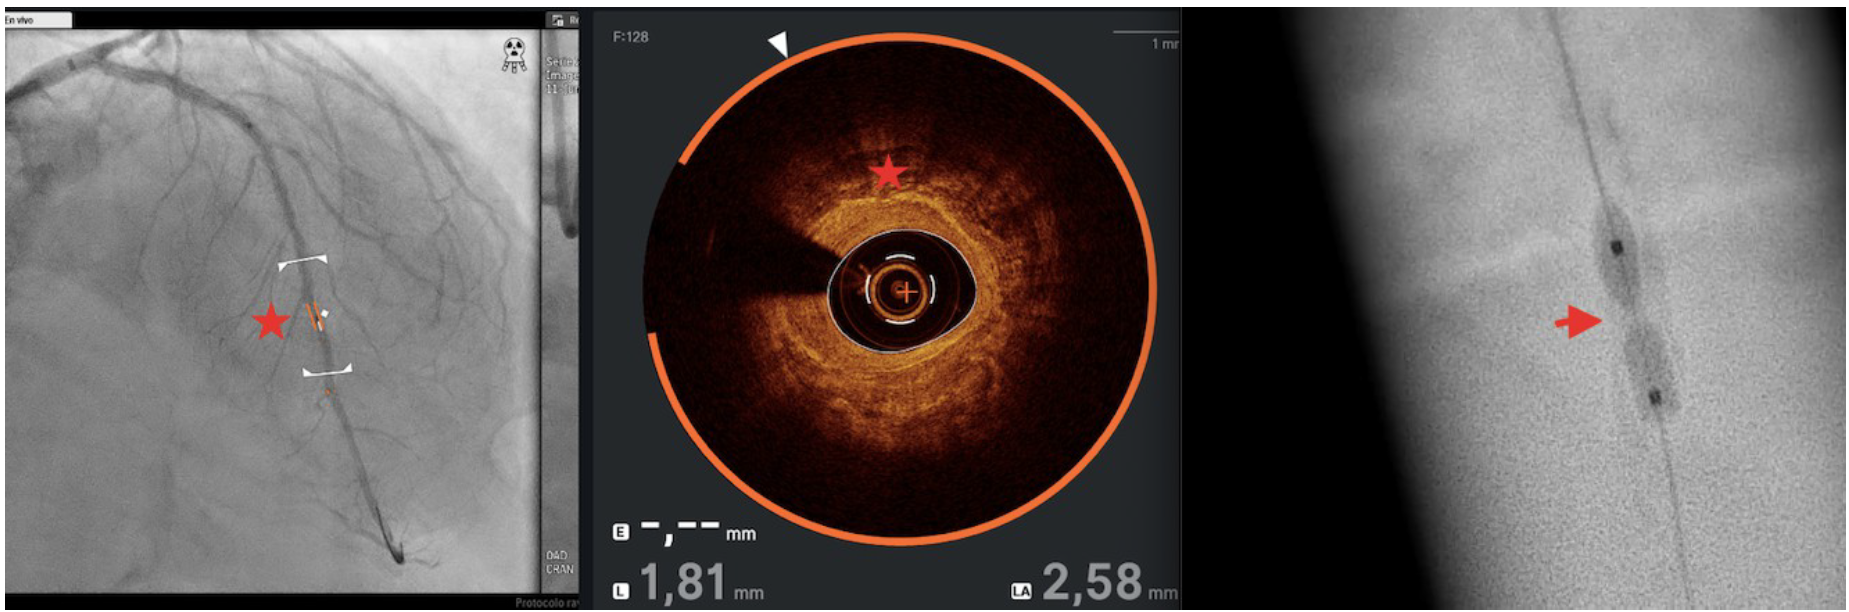

The distal lesion was treated in a deferred session using the LithiX Hertz Contact intravascular lithotripsy system (HC-IVL) (Elixir Medical) (Figure 5), which features a new intravascular catheter with mechanical contact indicated for fragmentation of newly appearing calcified, stenotic lesions in a coronary artery with moderate to serious calcifications before stent insertion. The LithiX HC-IVL’s unique design incorporates stainless steel hemispheres into a semi-compliant balloon; these hemispheres create different pressure points that help fracture calcified plaque via mechanical contact force.

After progressive dilations, maintaining pressures from 8 to 20 atm with a LithiX HC-IVL 2.5 x 10-mm balloon, dilation was performed with a 2.5 x 10-mm OPN NC PTCA balloon at 35 atm for 30 seconds and fracture of the calcium ring was achieved (Figure 6). The patient was discharged without complications or events during follow-up.